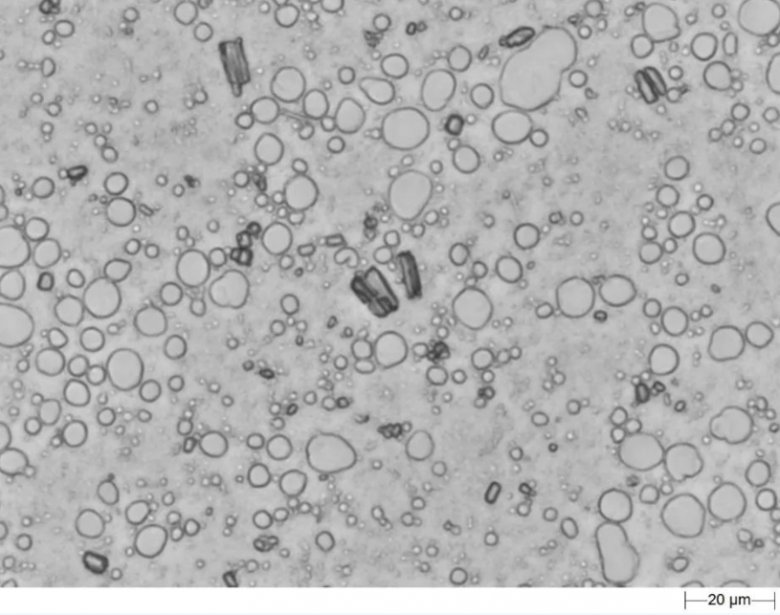

采用“三明治”制樣法,通過Morphologi 4自動掃描分析,二十分鐘之內即可獲得API顆粒和液滴顆粒的粒徑分布結果,以及API的晶癖和液滴顆粒的圓度值等形貌因子的分布值。

混懸型乳膏劑

Morphologi 4 自動掃描乳膏劑樣品